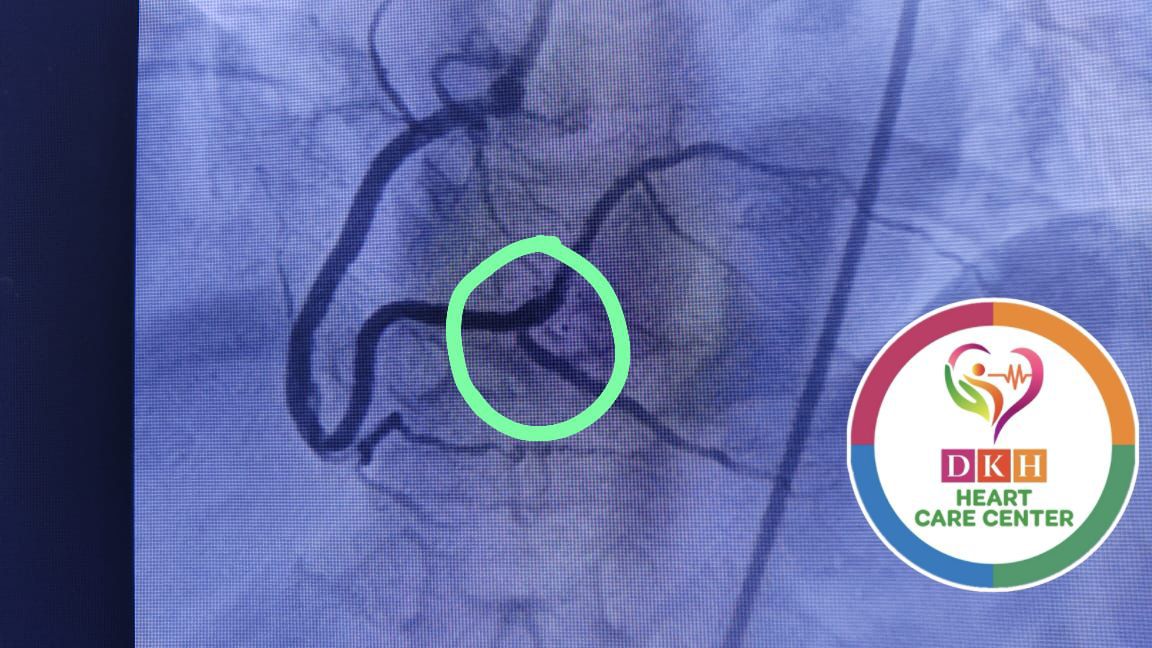

Deepa Kannan Hospital Heart Care Center & Cath Lab stands as a beacon of excellence in cardiovascular medicine. With state-of-the-art catheterization laboratory facilities and a team of renowned cardiac specialists, we are committed to providing comprehensive heart care services that combine cutting-edge technology with personalized patient care.

State-of-the-art cardiac catheterization laboratory with advanced imaging technology